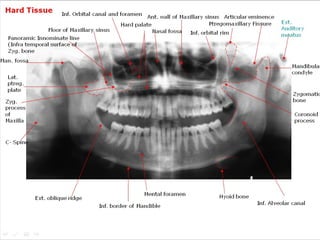

Hard Tissue

Inf. Orbital canal and foramen Ant. wall of Maxillary sinus Articular eminence

Ptregomaxillary Fissure

Hard palate

Floor of Maxillary sinus

Nasal fossa Inf. orbital rim

Panoramic Innominate line

(Infra temporal surface of

Zyg. bone

Man. fossa

Ext.

Auditory

meatus

Mandibular

condyle

Lat.

ptreg.

plate

Zygomatic

bone

Zyg.

process

of

Maxilla

Coronoid

C- Spine

Ext. oblique ridge

Mental foramen

Inf. border of Mandible

Powerpoint Templates

Hyoid bone

Inf. Alveolar canal

Hard Tissue Inf. Orbitalcanal and foramen Ant. wall of Maxillary sinus Articular eminence Ptregomaxillary Fissure Hard palate Floor of Maxillary sinus Nasal fossa Inf. orbital rim Panoramic Innominate line (Infra temporal surface of Zyg. bone Man. fossa Ext. Auditory meatus Mandibular condyle Lat. ptreg. plate Zygomatic bone Zyg. process of Maxilla Coronoid process C- Spine Ext. oblique ridge Mental foramen Inf. border of Mandible Powerpoint Templates Hyoid bone Inf. Alveolar canal Page 17